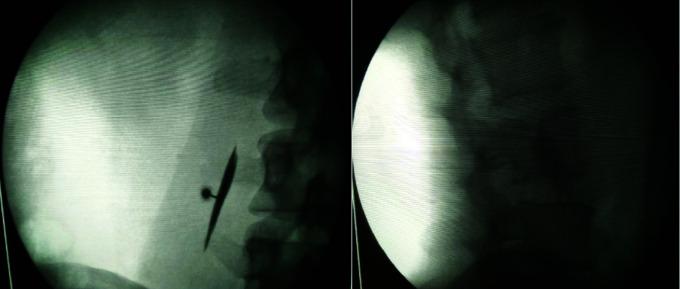

Thirty-six patients with chronic low back pain secondary to IP myofascial pain were randomly allocated into two groups and were given IP injection in prone position, using either FL or US as a guide. Pain scores were assessed using numerical rating scale (NRS); learning curve was evaluated by the number of attempts, time taken and subjective ease of performing the procedure. The psychological and quality of life assessment were done using Depression Anxiety Stress Scale (DASS) and Oswestry Disability Index (ODI), respectively.

FL and US guided IP injection had equianalgesic efficacy with a decrease in preprocedure NRS pain scores from mean value of 7.06 6 0.24 and 6.78 6 0.24, respectively, to 2.22 6 0.29 and 1.78 6 0.26 (at 24 hours), 1.50 6 0.22 and 1.50 6 0.23 (1 week), 0.50 6 0.12 and 0.56 6 0.15 (4 weeks) and 0.33 6 0.11 and 0.44 6 0.15 (12 weeks) (P < .001). The learning curve was easier for US intervention with average attempts of 1-2 compared to 1-3 for FL. The average time taken to perform IP intervention was lesser for US group. The improvement in DASS and ODI was comparable in both groups.

FL and US both are effective modalities for IP muscle injection as they provide equal relief from pain, disability and psychological stress. US guided IP injections are easier to learn and perform in comparison with FL.